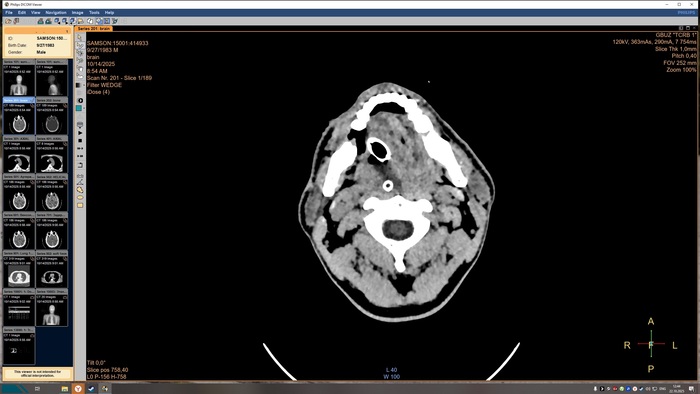

Описание КТ прикрепляю, а снимки будут в конце поста, по-другому у меня не получилось.

На топограмме, серии аксиальных срезов и реконструкций получены изображения суб- и

супратенториальных структур головного мозга от большого затылочного отверстия до крыши

черепа в нативном виде и в/в контрастированием. Определяются: справа четко

идентифицируемые внутричерепные интрапаренхиматозные гиперденсные неоднородные

очаги, копящее контрастное вещество, плотностью до 51-55ед.Х., размером: в проекции

лучистого венца 8х8х9 мм, в проекции продолговатого мозга 21х26х19 мм, Срединные

структуры мозга не смещены. Боковые желудочки: правый до 10,2 мм, левый до 12,9 мм,

третий-2,6 мм, четвёртый-13,8 мм. Селлярная и хиазмальная области без видимых

патологических изменений. Цистерны основания мозга, конвекситальные ликворные

пространства и борозды полушарий большого мозга сужены. Оболочки мозга без

особенностей. Миндалины мозжечка расположены соответственно возрасту. Дополнительных

образований и жидкостных скоплений в воздухоносных полостях височных костей с обеих

сторон, полости носа и его придаточных пазух не выявлено. Содержимое глазниц

визуализируется без особенностей. Признаков остеолитического, -пластического процессов,

аномалий развития и/или травматических повреждений костей черепа исследованного уровня

не выявлено. На прямой топограмме, серии аксиальных срезов и реконструкций получены

Заключение

КТ-признаки очаговых образований головного мозга. КТ-признаки правосторонней

верхнедолевой сегментарной б/пневмонии. ДИ ГОП.

Снимки КТ